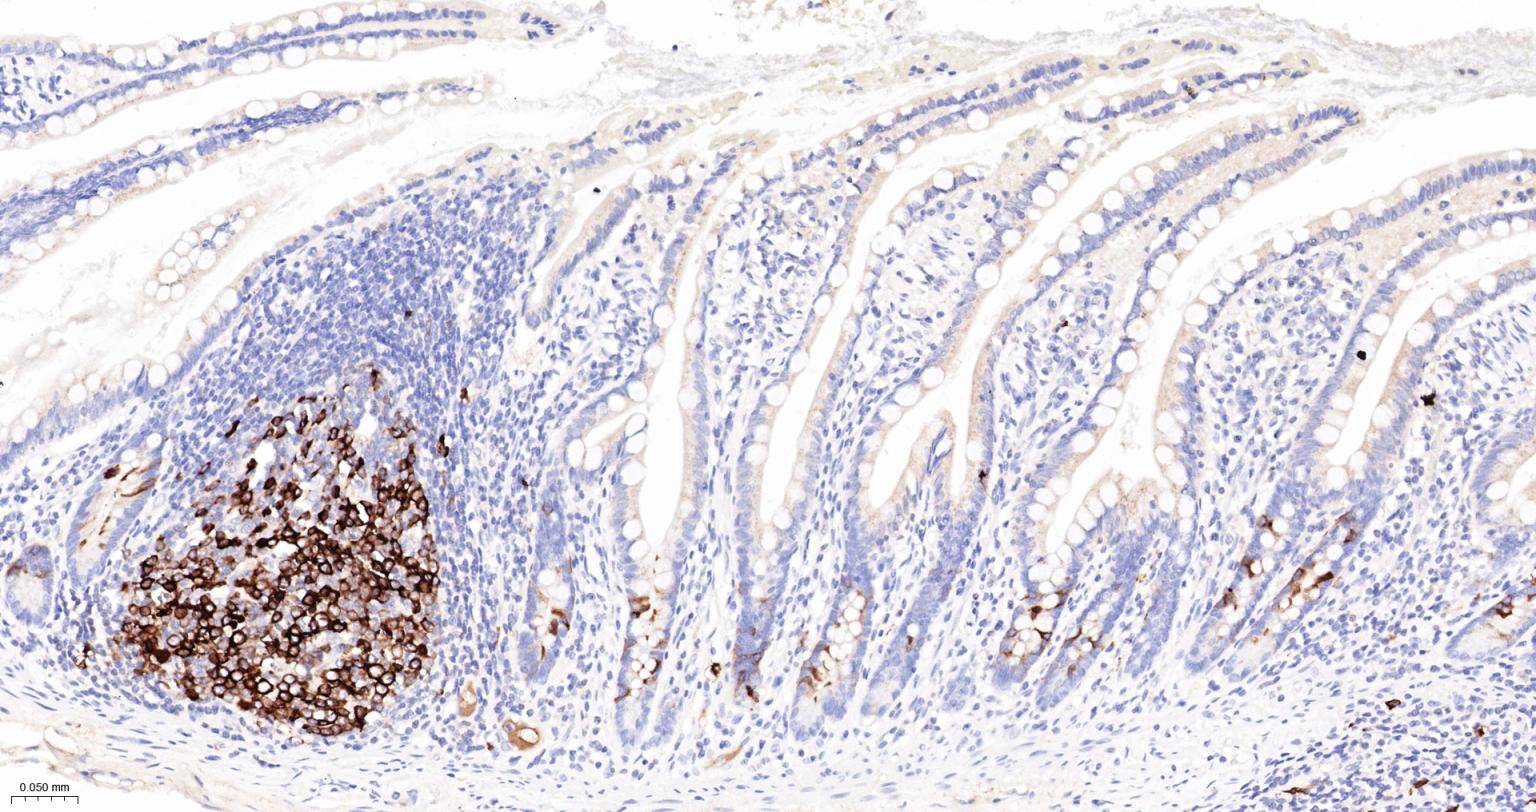

Paraformaldehyde-fixed, paraffin embedded Human Small Intestine; Antigen retrieval by boiling in sodium citrate buffer (pH6.0) for 15 min; The section was incubated with TACC3 Monoclonal Antibody, Unconjugated (bsm-61119R) at 1:200 overnight at 4°C, followed by conjugation to the bs-0295G-HRP and DAB (C-0010) staining.